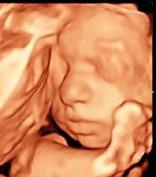

NÓGRÁD MEGYE 2022. október 10., XXXIII/41. Kandalló-, vegyeskazán-, gáz-, kondenzációs kémények építése KÉMÉNYÉPÍTÉS Telefon: 06-20/533-6565, 06-20/314-4209 BABAMOZI a legmodernebb 5D ultrahanggal! Nagy szeretettel várja két tapasztalt szonográfusunk a várandós kismamákat! Salgótarján, Március 15. utca 24. Telefonos előjegyzés: 06-20/532-0029 Nőgyógyászati, hasi és hüvelyi ultrahangot is végzünk! Dr. Al Ghaoui Nadim főorvos Tel.: 06-30/958-4303 Hétfőn és csütörtökön 16.00–19.00 óráig. Bejelentkezés: 06-70/206-3717, 32/420-111. NŐGYÓGYÁSZAT, GYERMEKNŐGYÓGYÁSZAT KLIMAX ÉS MEDDŐSÉG MAGÁNRENDELÉS RÁKSZŰRÉS, MÉHSZÁJFAGYASZTÁS Csecsemőés gyermekgyógyászati magánrendelés Dr. Nagypál Mária szakorvos Előzetesen telefonos bejelentkezés szükséges: 06-70/367-7001 Salgótarján, Pécskő út 25. Rendelés: hétfő, csüt. 17.00–19.00 óráig. UROLÓGIAI MAGÁNRENDELÉS Egerben és Gyöngyösön DR. KOVÁCS PÉTER Bejelentkezés: 06-70/676-3234 Salgótarján, Klapka György tér 1. Nyitva: 6–19-ig. A Privát max hálózat tagja NYITUNK! Október 12-én, 10 órakor A nyitás napján KEDVEZMÉNYEKKEL VÁRJUK kedves Vásárlóinkat! Részletek az üzletben! SIMON ÁRNYÉKOLÁSTECHNIKA 5–6–7 kamrás ablakok akciós árakon!